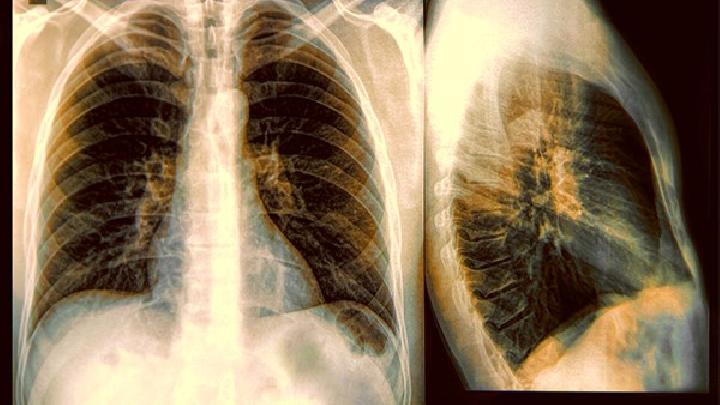

肺孢子菌病(sporotrichumschenskii)肺部慢性真菌病是常见的深部真菌病之一。患者急性,如急性细菌性肺炎发热咳嗽、咳痰、疲劳、胸部不适。